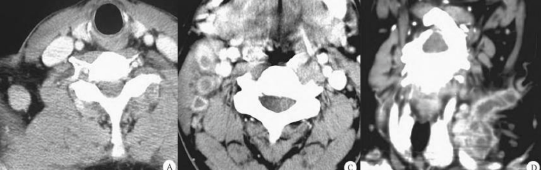

Fig.1

右侧颈静脉鞘上组见两枚肿大淋巴结,呈稍低密度,CT均值约39Hu,其中一枚淋巴结见结节状钙化,放射性摄取明显增高,SUVmax12.6。

Fig.2 PET/MR

示右侧颈静脉区淋巴结肿大,呈稍长T2信号,局部见结节状短T2信号,放射性摄取增高,suvm10.3;右侧胸锁乳突肌肿胀。左侧颌下见小淋巴结,放射性摄取轻度增高。